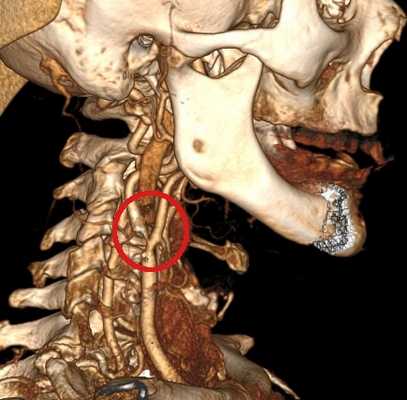

- КТ брахиоцефальных артерий с контрастированием. В заглоточном пространстве определяется накапливающая контраст извитая сонная артерия. При применении 3D-реконструкции на основе полученных срезов точность диагностики доходит до 100%.

- МРТ головного мозга. Проводится с контрастированием интракраниальных сосудов. Позволяет выявить церебральные ишемические очаги, оценить состояние веллизиева круга.